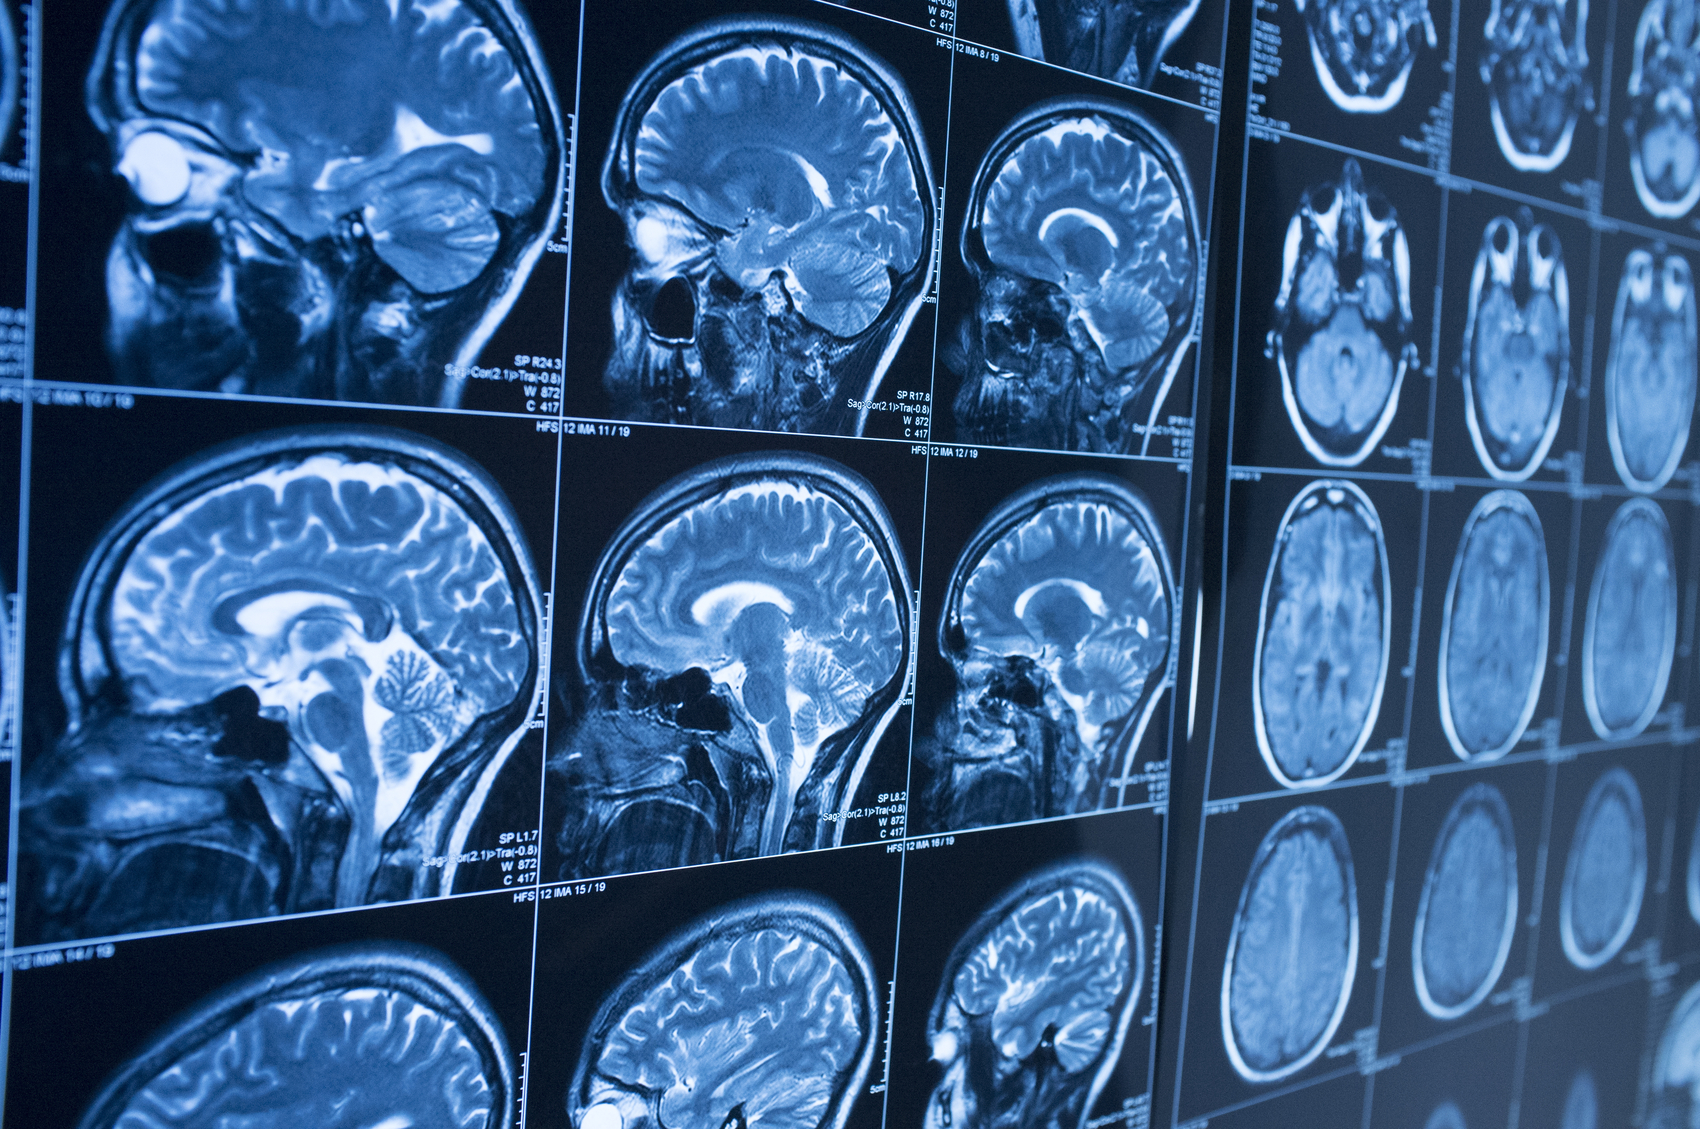

Traumatic brain injuries (TBIs) are often associated with dramatic accidents and immediate loss of consciousness. In reality, many TBIs are far more subtle. People can suffer a brain injury in a car crash, a slip and fall, or other accident without realizing the severity of what happened. Symptoms may appear gradually, worsen over time, or be mistaken for stress or exhaustion, which is why TBIs frequently go undiagnosed in the early stages.

A traumatic brain injury occurs when a sudden blow, jolt, or impact disrupts normal brain function. TBIs range from mild injuries, such as concussions, to severe injuries that cause long-term or permanent impairment. Even a “mild” TBI can have serious consequences if left untreated.

Many people assume a head injury only counts as a TBI if there is visible trauma or loss of consciousness. That is not always the case. Brain injuries can occur even when the head does not directly strike an object, such as during whiplash-type movements in motor vehicle accidents.